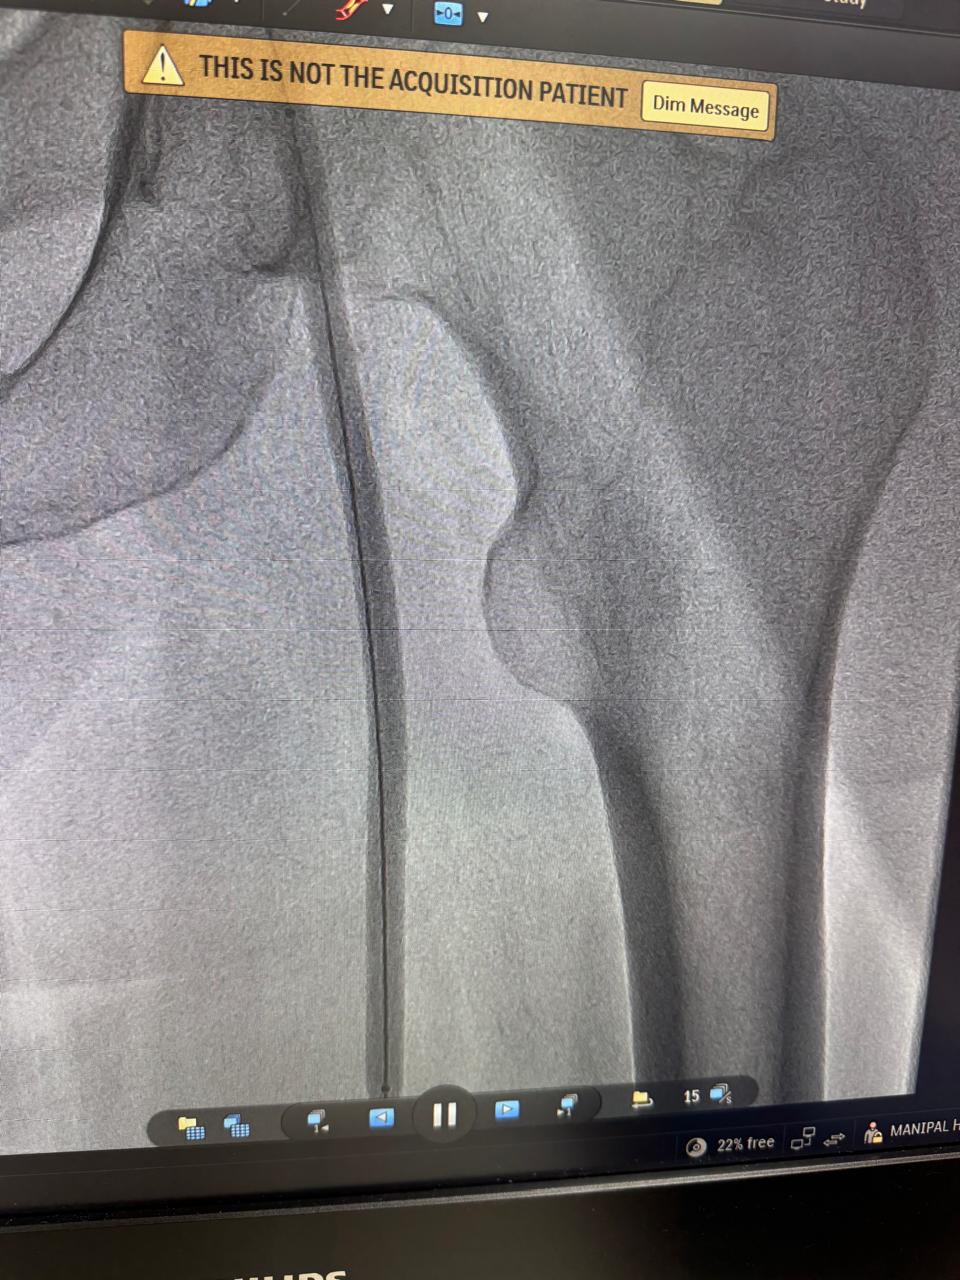

Renal Artery Stenting

Rental Artery Stanting 1

Rental Artery Stanting 2

Rental Artery Stanting 3

Rental Artery Stanting 4